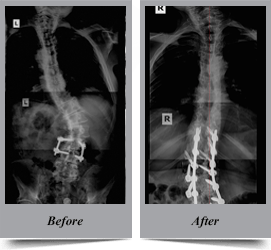

Congenital Scoliosis

Congenital scoliosis is the lateral curvature of spine that occurs in children